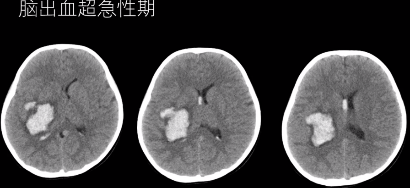

(1)超急性期 CT 高密度;T1WI 呈等或略低信号,T2WI 呈高信号。

(上下滑动查看全部图片)